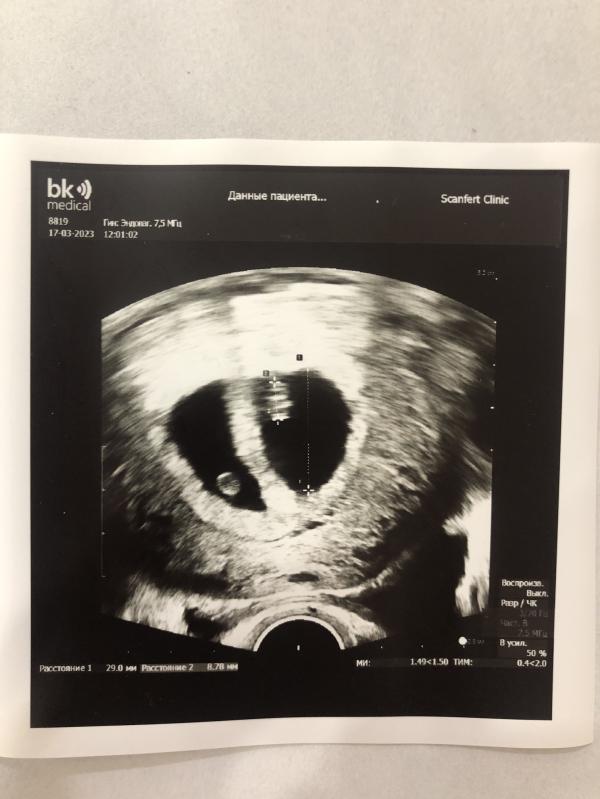

6-7 недель беременности , сегодня слушали сердечки❤️❤️